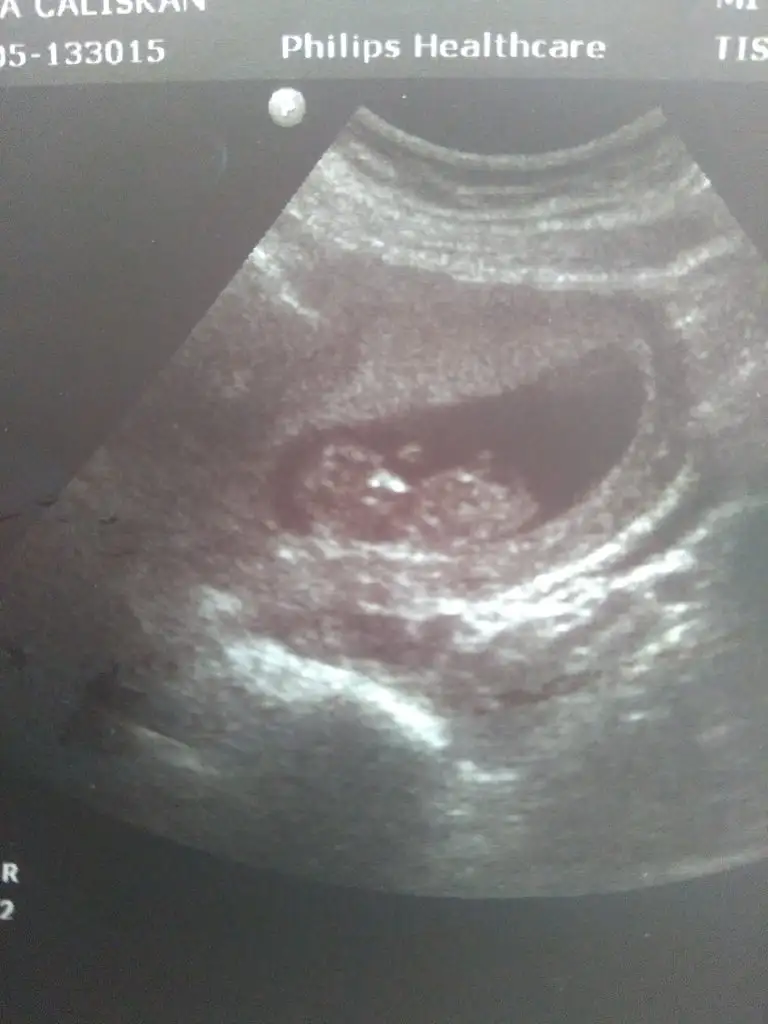

Merhaba millet

Ramzi teorisine göre cinsiyet tahmini yapacagim ilk ultrasyon resminizi atin bakiyim. Eger cinsiyetiniz belliyse hic söylemeeyin bakalm dogru tahmin edebilecekmiyim daha dogrusu ramzi teorisi hakli cikacak mi?

Eklentiler

• 16133946752565419132069191401812.webp

16133946752565419132069191401812.webp

22,4 KB · Görüntüleme: 91